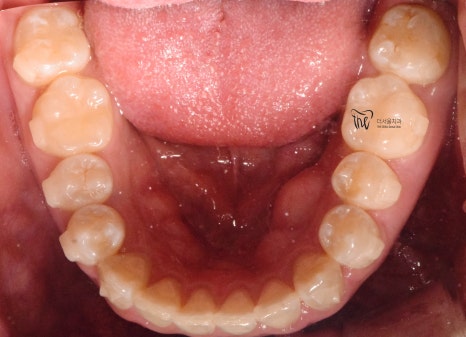

구강 내 사진을 보면, 전형적인 Open bite 의

형태를 띄고 있는 것을 보실 수 있습니다.

그 정도는, 그렇게 심하지는 않으나

치아교정 을 받지 않는다면 턱관절 에

더 큰 문제를 일으킨다는 것을 본인 스스로도

잘 알고 있었기 때문에 저에게 진료를

의뢰했었습니다.